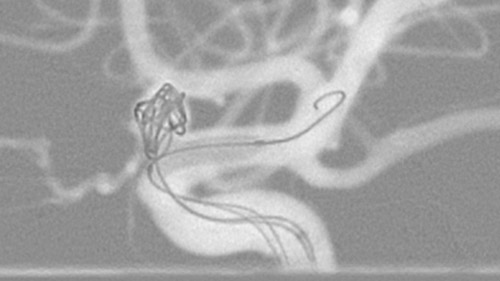

Live 3D Roadmap allows you to follow the advancement of guidewires, catheters and coils in real-time. It automatically adapts in real-time to changes in C-arm angulation and rotation, table movement, field of view and source-image distance.